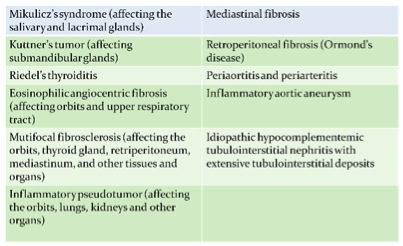

IgG4-related disease is a fibroinflammatory condition characterized by tumefactive lesions, dense lymphoplasmacytic infiltrate rich in IgG4-positive plasma cells, storiform fibrosis, and, often but not always, elevated serum IgG4 concentration. It was initially described mainly focus on pancreas, and recognized as systemic condition in 2003 when extra-pancreatic manifestations were identified in patients with autoimmune pancreatitis (1). There was a list of previously recognized conditions now acknowledged to fall into the spectrum of IgG4-related disease (table 1). IgG4-related disease mainly occurred in male (62-83%), with majority more than 50 years old (2). Until 2004, two cases of IgG4-related lung disease were published, describing 2 men with autoimmune pancreatitis who were found to have lung parenchymal infiltrates incidentally. There serum IgG4 levels were elevated and lung infiltrates responded with oral prednisolone.

There is still no published consensus about the diagnostic criteria of igG4-related disease. Most studies are using diagnostic criteria by Umehara and colleagues in 2011: 1) clinically showing characteristic diffuse or localized swelling or masses in single or multiple organs, 2) hematological examination shows increased serum IgG4 concentration, 3) histopathologic examination showing a) marked lymphocyte and plasmacytic infiltration and fibrosis, and, b) infiltration of IgG4 + plasma cells: ratio of IgG4+/IgG+ cells more than 40% and more than 10 IgG4+ plasma cells per high power field. Patient can be diagnosed as definite (fulfill all 3 criteria), probable (fulfill the 1st and 3rd criteria), and possible (fulfill the 1st and 2nd criteria) IgG4-related disease (3). According to 2 series from Japan, the incidence of lung involvement of IgG4-related disease can range from 14 to 54% (4,5). There are two relatively large scale case series published by Matsui S in Respirology 2013 and Zen Y in Am J Surg Pathol 2009 to describe the clinical features of patients with IgG4-related lung disease. Both series showed male predominance around 80%. There were 12% and 43% of patients in respective series having allergic history like rhinosinusitis and asthma. Only 28% and 47% of patient in respective series having pulmonary symptoms and mostly complained cough. The radiological features of lung manifestation were described in Zen study, which can be nodular, bronchovascular interstitial, ground-glass opacity or pleural lesion. (table 2,3) The possible radiological findings of IgG4-related lung disease were also described in review article by Ryu in Eur Respi J 2012 (table 4) (6).